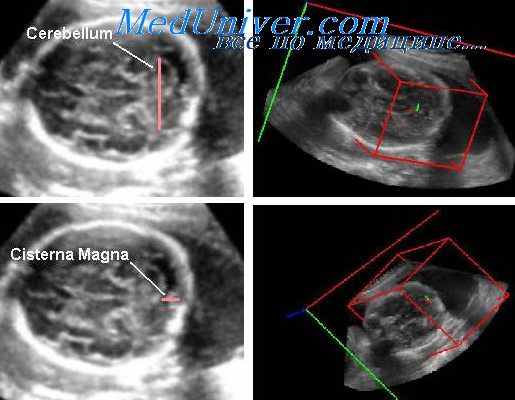

Обследовано 525 женщин с правосторонним (187 пациенток), левосторонним (133 пациентки) и амбилатеральным (205 пациенток) расположением плаценты в сроки 37-40 недель физиологически протекающей беременности в различные сезоны года. У всех женщин проводили двумерное ультразвуковое исследование фетометрических показателей и плацентарной латерализации, допплерометрическое исследование кровотока (систоло-диастолическое отношение Vs/Vd) в пуповинной, правой и левой маточных артериях (УЗ-приборе «Toshiba (Eccocee) SSA-340» (Япония), 3,5 МГц, с цветным допплеровским картированием, регистрационное удостоверение ФС № 2005/1686). Сократительная активность матки регистрировалась с симметричных участков правой и левой половин живота на уровне пупочного кольца беременных при помощи наружной механогистарографии (два кардиотокографа «Сономед-200»). При ультразвуковой фетометрии определялись: бипариетальный размер головки плода (БПР), окружность головки (ОГ), длина бедренной кости (ДБ), окружность живота (ОЖ).